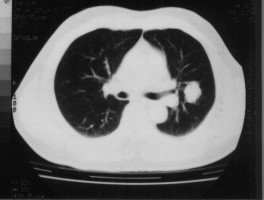

图A: 治疗前右肺中央型肺腺癌,约5X6厘米。

图B:治疗后肿块明显缩小,约2X2厘米。

图C: 治疗前右肺中央型肺鳞癌,约8X6厘米。

图D:治疗后肿块完全消失,病人CR(无瘤生存)2年。